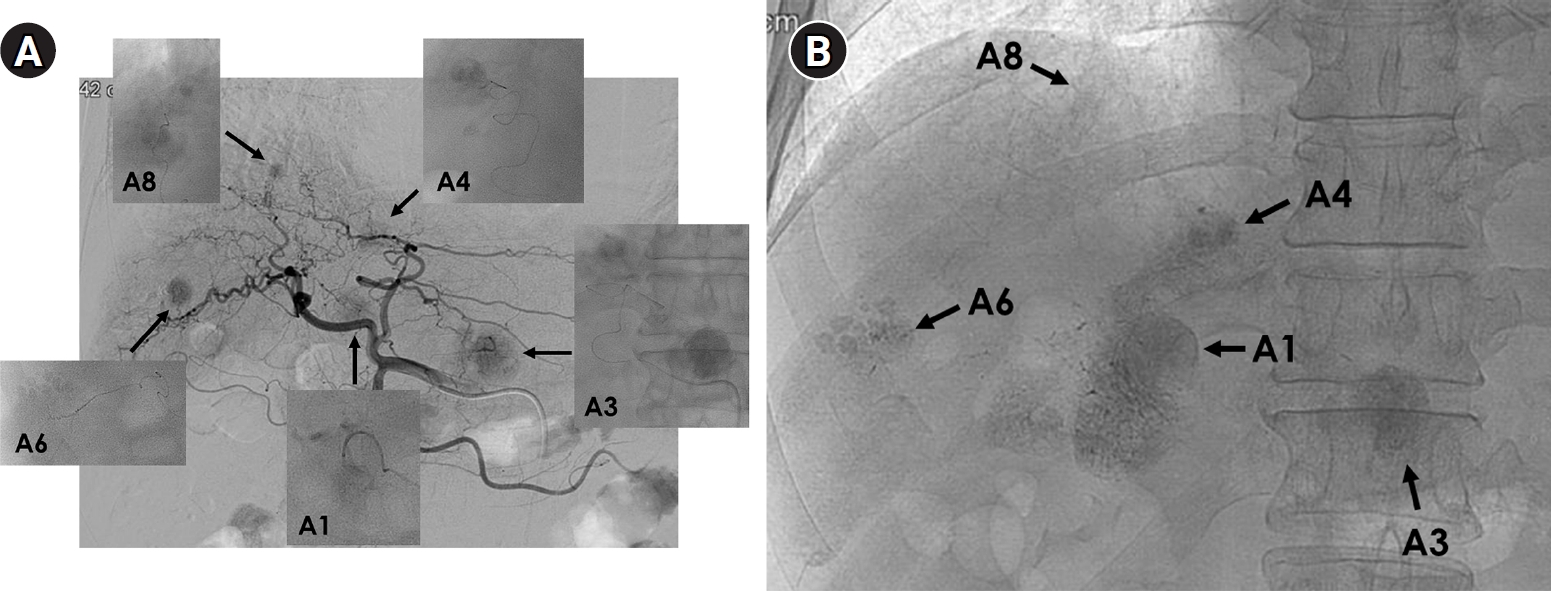

Fig. 4.

Superselective transarterial chemoembolization (TACE) for five nodular tumors in a 60-year-old man. (A) Common hepatic arteriography shows five nodular tumors. Superselective TACE was performed through tumor-feeding arteries including A1, A3, A4, A6, and A8. (B) Post-TACE fluoroscopy shows dense lipiodol uptake within the tumors without significant parenchymal deposition.

kjir-2025-00066f4.jpg

Fig. 4. Superselective transarterial chemoembolization (TACE) for five nodular tumors in a 60-year-old man. (A) Common hepatic arteriography shows five nodular tumors. Superselective TACE was performed through tumor-feeding arteries including A1, A3, A4, A6, and A8. (B) Post-TACE fluoroscopy shows dense lipiodol uptake within the tumors without significant parenchymal deposition.